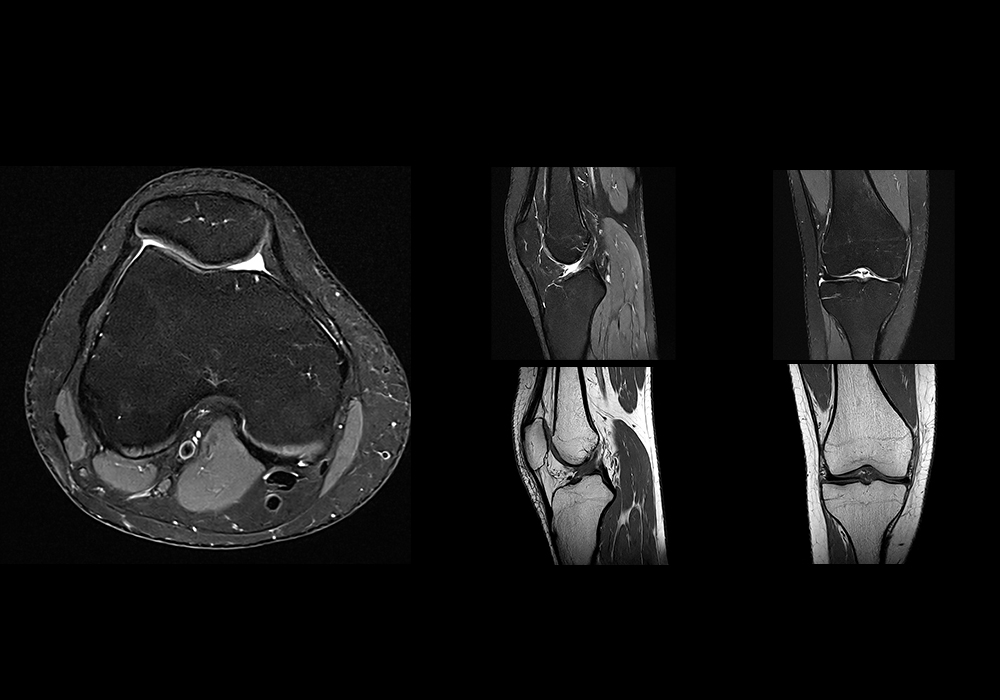

- Lesões articulares: condromalácia patelar, lesões de menisco, derrame articular.

Protocolos de exame

Os protocolos de RM para lesões esportivas variam de acordo com a área a ser examinada, mas normalmente incluem sequências T1, T2, STIR ou PD Fat Sat, que permitem identificar tanto a anatomia normal quanto as alterações patológicas.